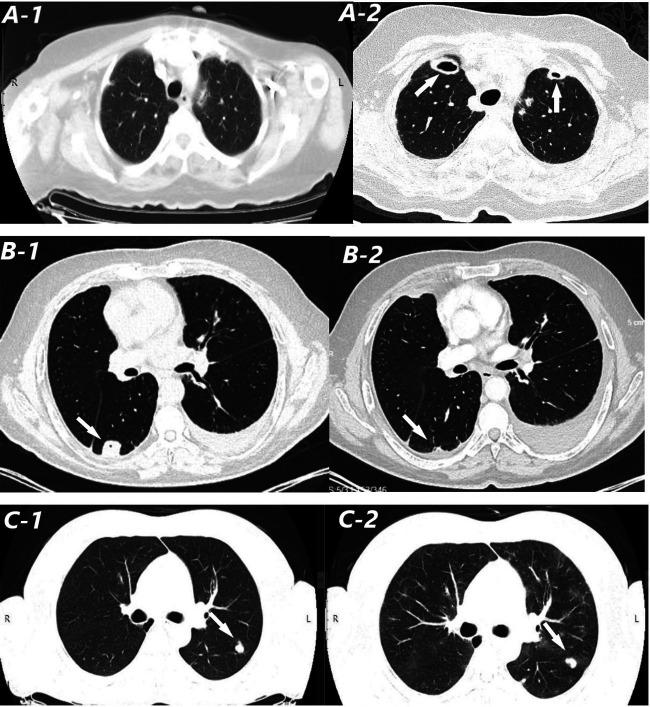

Electronic health records of RA patients who had LNs detected on computed tomography (CT) between January 2015 and December 2020 were evaluated retrospectively. Patients with follow- up CT images were included in the study. Baseline and follow-up images were meticulously examined for the number, size, attenuation, and cavity formation. Clinical, histopathologic, and laboratory find- ings were analyzed.

Forty-two RA patients with LNs were studied, 21 were on bDMARDs/tofacitinib (11 females, mean age: 59.7 6 8.4) and 21 were on csDMARDs (12 females, mean age: 71.4 6 8.3). The proportion of patients with progressed nodules during follow-up was comparable between groups (six patients in bDMARDs/tofacitinib vs seven patients in csDMARDs). Progression of LNs was observed in six patients in the bDMARDs/tofacitinib group: three in anti-TNFa, two in rituximab, and one in abatacept users and none in tofacitinib users.